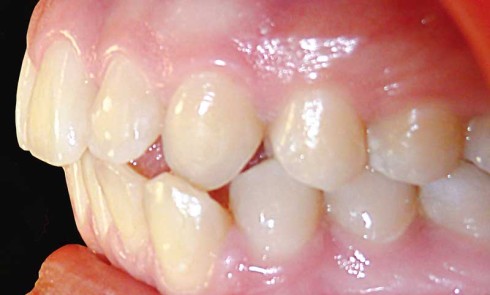

Article réservé à nos abonnés Diagnostic des malocclusions simples

L’Orthopédie Dento-Faciale est une discipline de l’art dentaire bien souvent oubliée de l’omnipraticien. L’orthodontiste voit arriver en consultation des patients...